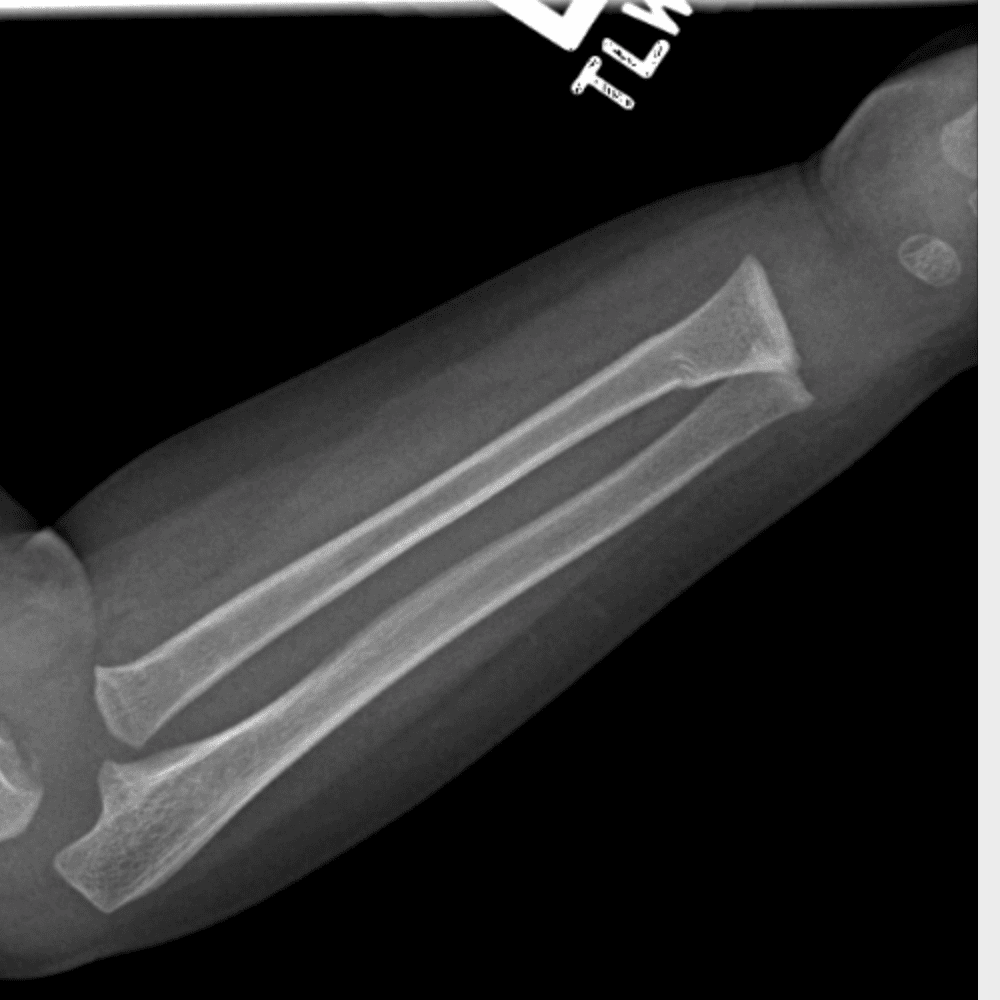

Simulates call by including subtle or difficult cases and some normals.

30 cases